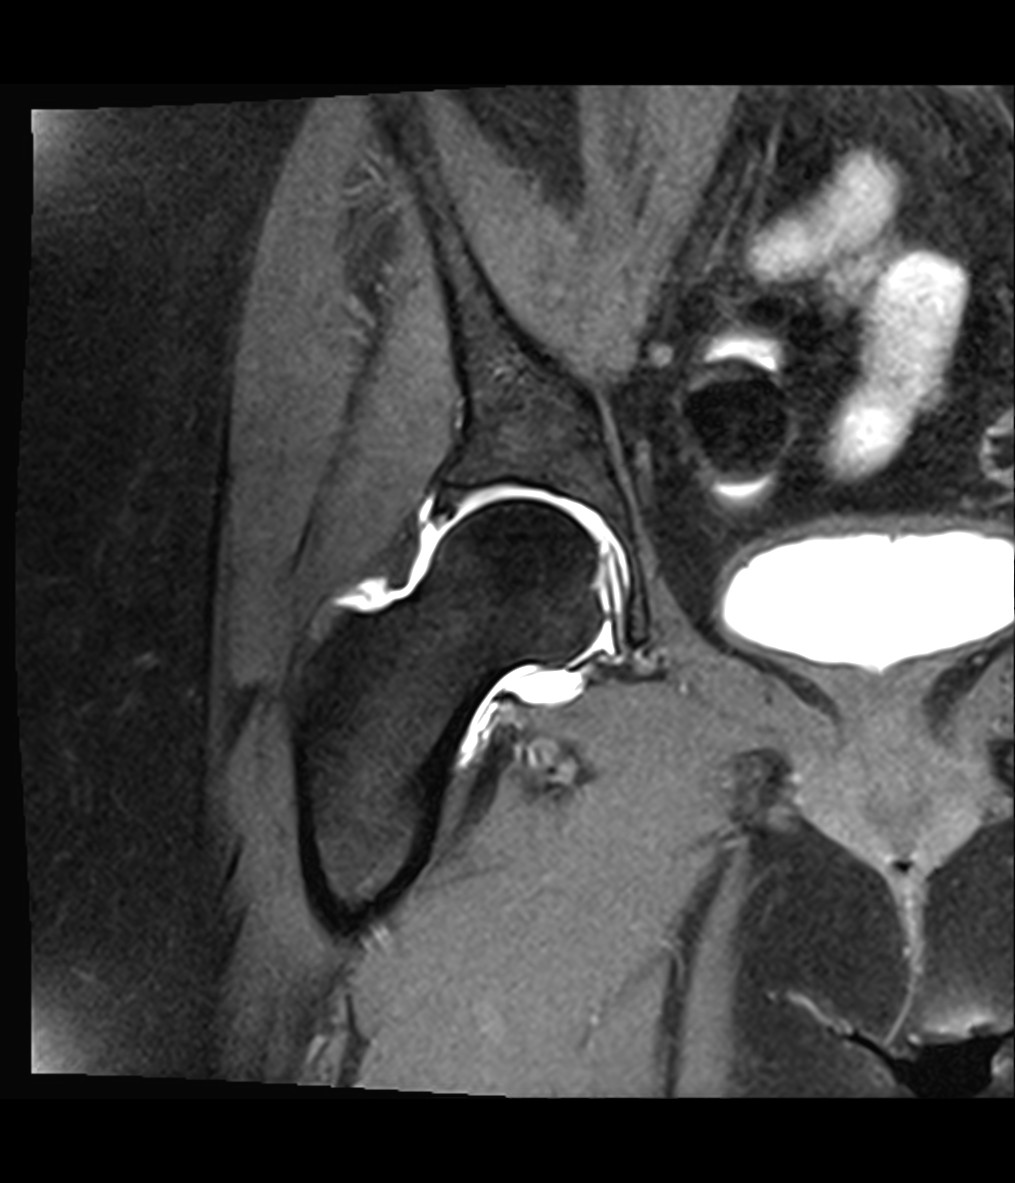

NAPRAWA OBRĄBKA STAWU BIODROWEGO

Uszkodzenie obrąbka stawowego stawu biodrowego jest częstą przyczyną dolegliwości bólowych zlokalizowanych w pachwinie zwłaszcza u młodych aktywnych osób. W Ortho Sport Clinic stosujemy metodę leczenia z wykorzystaniem miniartrotomii do stawu biodrowego co skraca czas zabiegu, redukuje ilość wykorzystywanego promieniowania X podczas operacji oraz zapewnia doskonały wgląd do stawu biodrowego w razie potrzeby przeprowadzenia dodatkowej procedury.

Przed przystąpieniem do zabiegu konieczna jest konsultacja z jednym z naszych lekarzy, który zbierze ogólny wywiad, oceni stan ogólny kliniczny pacjenta, zleci wykonanie MRI stawów biodrowych oraz konieczne badania niezbędne do kwalifikacji. Pacjent nie wymaga specjalnego przygotowania do tego typu zabiegu.